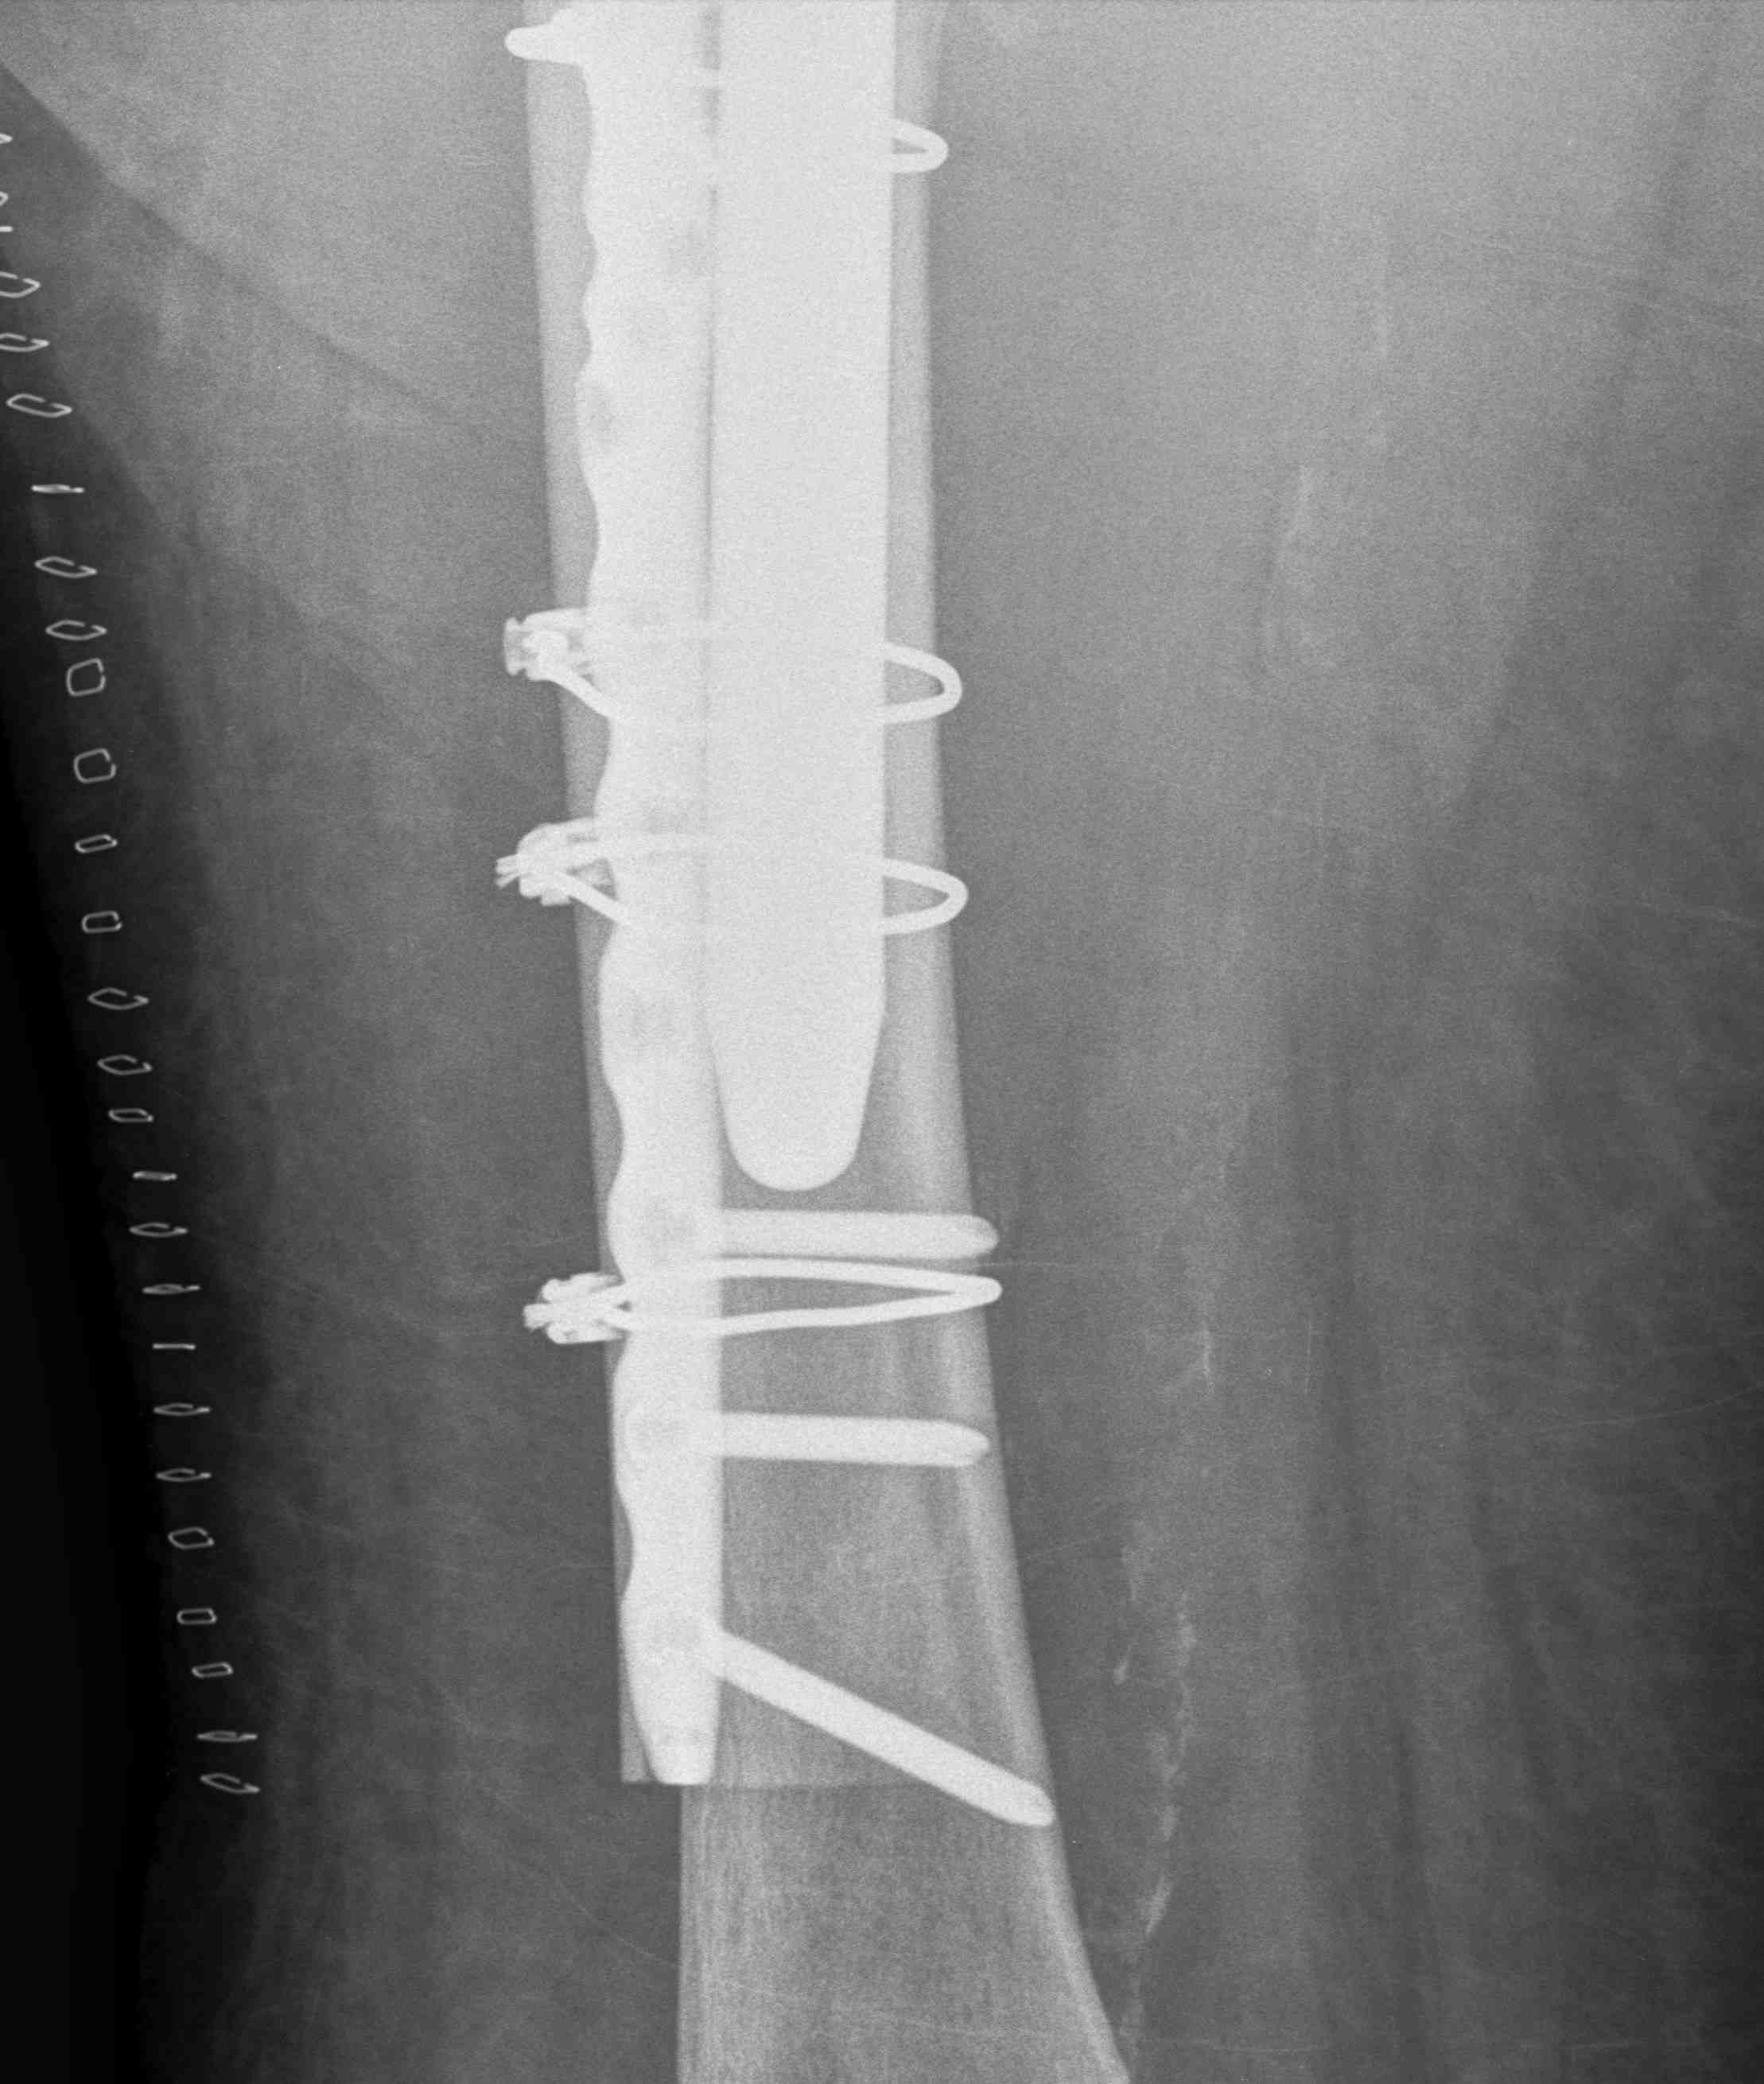

ORIF with locking cable plate and +/- Cortical strut allograft

Contoured anatomical fit with trochanteric extension

Variable angle locking screws to go around implants

Cable options

Unicortical screw options

ORIF Locking cable plate +/- cortical strut allograft

- overlap femoral implant

- to distal femur